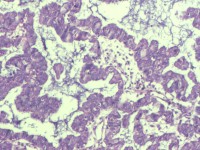

性别

女

年龄

55岁

临床诊断

异常子宫出血

一般病史

阴道不规则出血1月

标本名称

子宫内膜

大体所见

灰白色组织1堆、4*3.4*2.2CM大。

能诊断癌吗

子宫内膜样腺癌